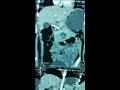

نجح فريق طبي في مستشفى الأطفال الجامعي التابعة لجامعة المنصورة، من استخراج "دبوس" من معدة طفل ابتلعه منذ نحو أسبوعين وتسبب في آلام داخل البطن.

من جانبه أكد الدكتور أحمد الرفاعي، مدير مستشفى الأطفال، أنه جرى استقبال الطفلة التي تبلغ من العمر 9 سنوات، بعد أن ابتلعت "دبوس" منذ أسبوعين، وبالكشف الطبي عليها تبين أن الدبوس اخترق جدار المعدة.